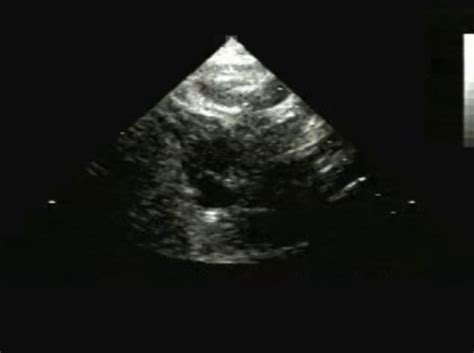

To confirm the diagnosis, doctors will use a variety of diagnostic tools. An echocardiogram (echo) is the primary tool used to visualize the heart’s structure and function. This ultrasound of the heart can clearly show the underdeveloped or absent aortic valve, the size of the heart chambers (especially the often-small left ventricle), and how blood is flowing (or not flowing) through the heart. Other tests might include an electrocardiogram (ECG or EKG) to check the heart’s electrical activity and rhythm, and a chest X-ray to look at the size and shape of the heart and lungs. In some cases, especially if the diagnosis is unclear or further detail is needed, a cardiac MRI or even cardiac catheterization might be performed. These advanced imaging techniques provide incredibly detailed pictures of the heart and its blood vessels, helping the medical team understand the full extent of the defect and plan the best course of treatment. The goal is always to identify this condition as quickly and accurately as possible, as prompt diagnosis is paramount for survival and successful management. The ICD 10 code Q23.0 serves as the official identifier once this diagnosis is confirmed.